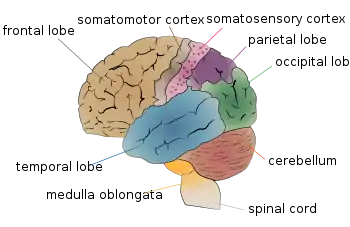

| Cerebellum (labeled bottom right) of the human brain. It is located above the brain stem, posterior to the brain. | |

Cerebellar degeneration is a condition in which cerebellar cells, otherwise known as neurons, become damaged and progressively weaken in the cerebellum.[1] There are two types of cerebellar degeneration; paraneoplastic cerebellar degeneration, and alcoholic or nutritional cerebellar degeneration.[2] As the cerebellum contributes to the coordination and regulation of motor activities, as well as controlling equilibrium of the human body, any degeneration to this part of the organ can be life-threatening. Cerebellar degeneration can result in disorders in fine movement, posture, and motor learning in humans, due to a disturbance of the vestibular system. This condition may not only cause cerebellar damage on a temporary or permanent basis, but can also affect other tissues of the central nervous system, those including the cerebral cortex, spinal cord and the brainstem (made up of the medulla oblongata, midbrain, and pons).[2]